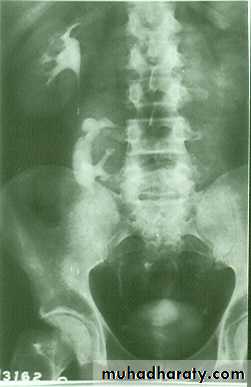

IVU shows :

The kidneys at low position .

Close to the spine with long axis parallel to the spine .

Mal–rotation manifested by medially directed calyces.

The renal pelvis and ureters are anterior and lateral in position .

HORSE –SHOE KIDNEY

HORSE SHOE KIDNEY